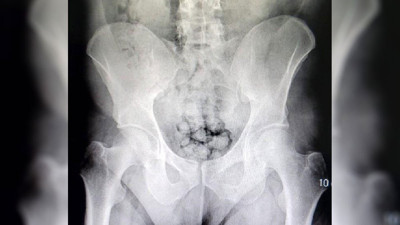

12 kapsül metamfetamin İranlının bakın neresinden çıktı Ağrı'da uygulama esnasında durdurulan bir araçta İran uyruklu olduğu öğrenilen şahsın bağırsak ve makat kısmında kapsül şeklinde 12 adet metamfetamin maddesi ele geçirildi.